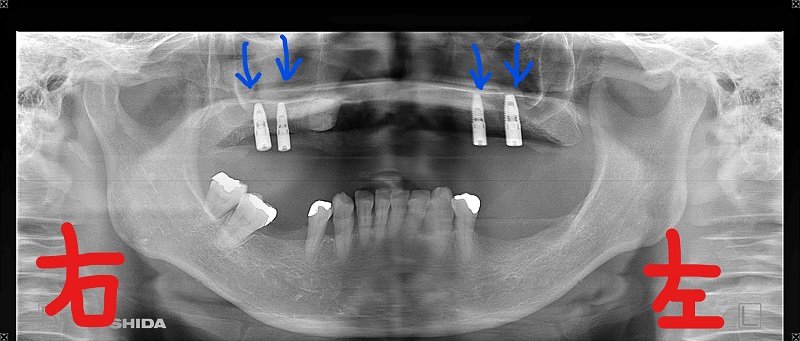

左の写真は入れ歯を外した状態の上顎を下から見上げたもので、右のレントゲン写真では、4つの青色矢印が示す位置にロケーターアタッチメント(ゴールド色の部品)が確認できます。これらはインプラントに装着されており、入れ歯の内側にあるキャップと結合することで安定性を高めます。